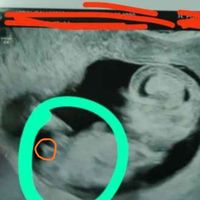

Hola chicas!! Me he decidido a abrir este debate porque veo que muchas os acercáis a mamis julio a preguntarme por el sexo. No soy gine ni nada de eso, eh? Y os aviso de que hay margen de error, pero...